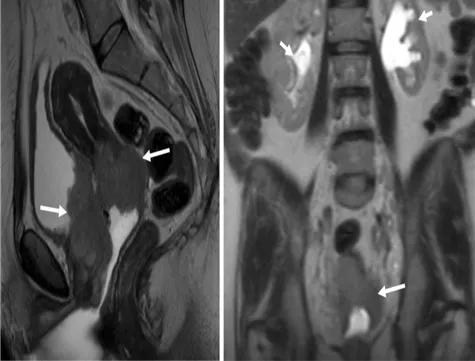

52세 여성이 비정상 자궁 출혈로 내원하였다. 자궁경부 조직 검사 결과 침윤성 편평상피암으로 진단되었다. 골반 MRI 사진이다. 가장 적절한 치료는 무엇인가?

Hydronephrosis 소견이 관찰되어 stage IIIB 이상이므로 CCRT를 시행한다.

• 자궁경부암으로 진단되어 병기 설정, 치료 계획을 위하여 골반 MRI를 촬영한 것으로 보인다.

• MRI 상 종양이 질 하부 1/3과 parametrium을 침범하였으며, 종양으로 인한 bilateral hydronephrosis도 관찰된다.

• 따라서 최소 stage IIIB(pelvic wall 침범 or hydronephrosis)로 진단 가능하다.

• Stage IIB 이상의 자궁경부암은 수술 없이 CCRT(concurrent chemoradiotherapy)를 시행한다.